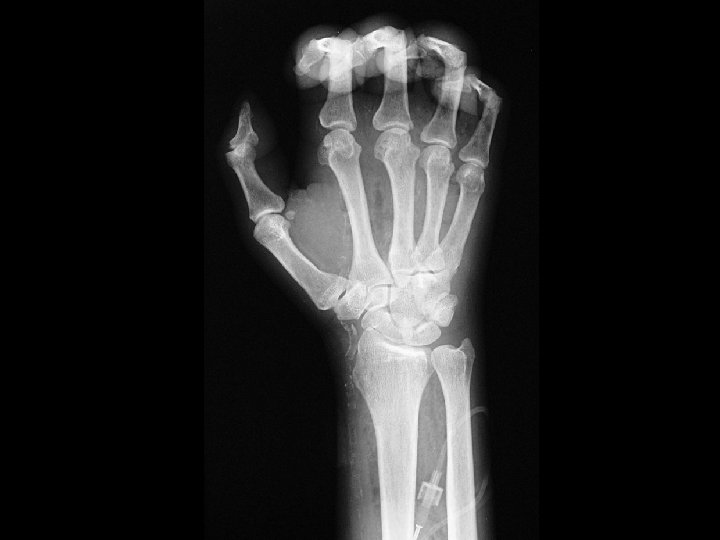

CPPD • Findings: – Bilateral wrist and 1 st – 3 rd MCP joint space narrowing – Small hook-like osteophytes of the MC heads – Chondrocalcinosis of the wrist • ddx: – hemochromotosis